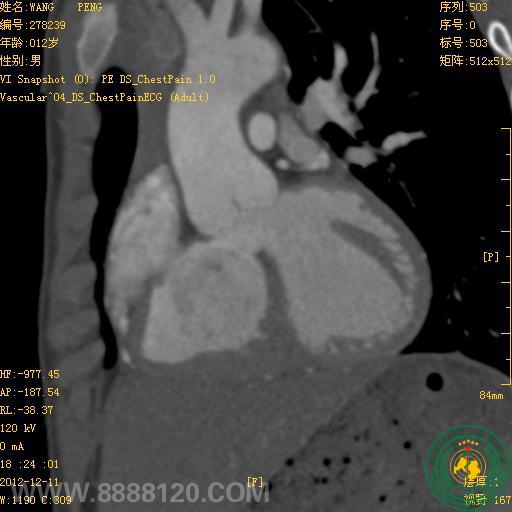

我院炫速双源CT正式投入使用第二周,今天即对1例高心率(114次/分钟)法洛氏五联症合并动脉导管未闭患者作了心脏、冠状动脉、主动脉和肺动脉检查,一次扫描,快速、准确诊断。

1.右心室增大,室间隔干下部缺损,房间隔卵圆孔缺损,主动脉骑跨室间隔,肺动脉主干和右室流出道狭窄,诊断为法洛氏五联症,双侧下肺动脉明显加宽。

2.主动脉弓和肺动脉主干间见通道,诊断为动脉导管未闭。

3.左、右冠状动脉未见异常。

炫速双源CT(又称第二代双源CT或新双源CT)与128排、320排CT比较,其时间分辨率最高,达75ms,在显示心腔外解剖结构,如肺动脉、肺静脉、冠状动脉、主动脉弓降部和降主动脉有体肺侧支的发育及畸形时具优势。临床应用经验证明,DSCT能准确显示婴幼儿的心血管解剖,特别有利于复杂型先天性心脏病的节段分析,以提供诊断和手术依据,在心脏与内脏关系、房室连接关系、大血管起止排列关系、肺动脉发育状况、冠状动脉发育状况、主动脉弓发育状况及肺静脉畸形引流诊断方面具有优势。婴幼儿进行心导管检查受限,但行CT检查也要考虑其辐射剂量问题。对于婴幼儿我们采用大螺距前瞻性心电门控技术(即新双源CT特有的炫速螺旋扫描),其可使检查有效辐射剂量由回顾性门控的平均5.0 mSv降到0.7 mSv左右,值得临床推广应用。